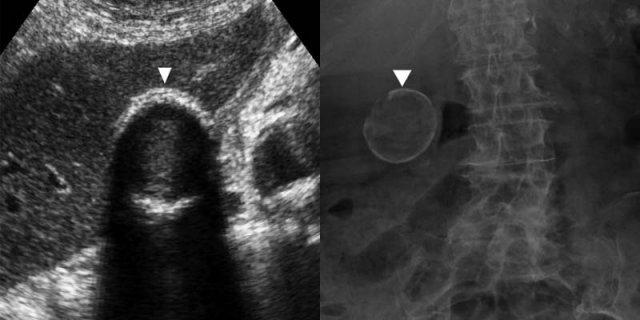

Bên trái là nam giới 74 tuổi bị suy tim phải sung huyết.

Siêu âm cho thấy dày thành lan tỏa của túi mật không có sỏi và không đau, kèm theo các tĩnh mạch gan (đầu mũi tên) và tĩnh mạch chủ dưới giãn lớn, là bằng chứng hỗ trợ chẩn đoán suy tim phải.